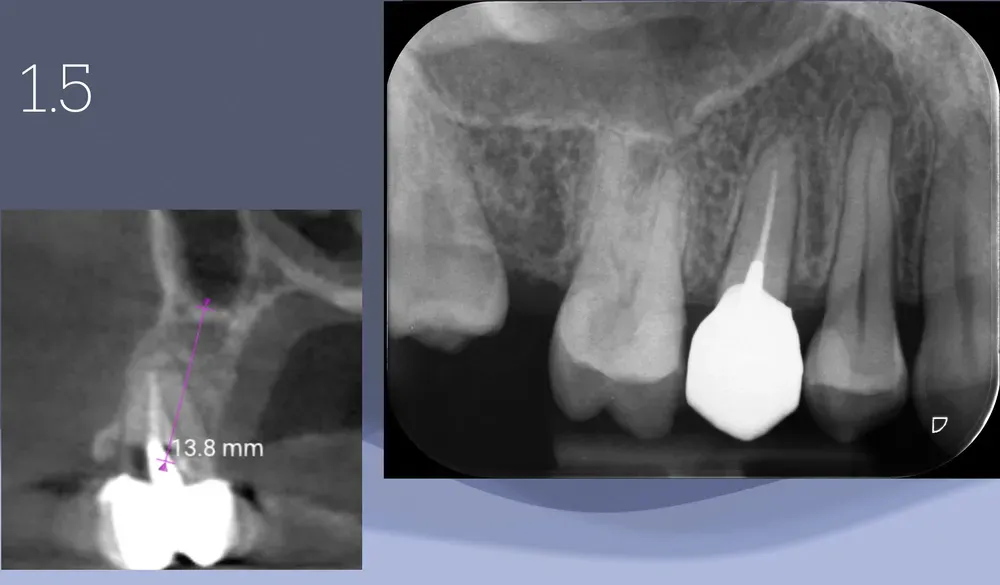

Illustrazione radiografica dell

Illustrazione radiografica dell’asse da correggere in un caso di premolare superiore con frattura radicolare.